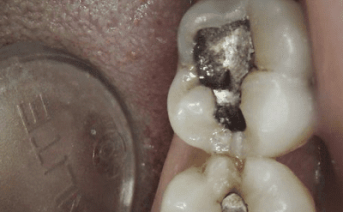

Our composite dental fillings in Atlanta, Georgia, not only fill in cavities, but can treat various cosmetic treatments by filling in teeth that have been damaged or demineralized. Schedule your treatment at Smiles of Atlanta with our dentist, to see if you need a composite dental filling from Dr. Ed Trizzino. Call 770-777-0808 today.